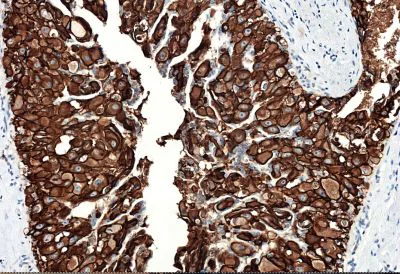

Immunohistochemistry (Formalin/PFA-fixed paraffin-embedded sections) - Anti-ErbB2 / HER2 antibody [CAL27] - BSA and Azide free (AB251602)

Immunohistochemical analysis of human breast carcinoma tissue labeling ErbB2 / HER2 with ab237715 at 1/2000 dilution, followed by Rabbit specific IHC polymer detection kit HRP/DAB (ab209101). Positive staining on the human breast carcinoma is observed. Counter stained with hematoxylin.

Secondary antibody only control : Used PBS instead of primary antibody, secondary antibody is Rabbit specific IHC polymer detection kit HRP/DAB (ab209101).

Heat mediated antigen retrieval with Tris-EDTA buffer (pH 9.0, epitope retrieval solution 2) for 20 mins.

The section was incubated with ab237715 for 10 mins at room temperature.

The immunostaining was performed on a Leica Biosystems BOND® RX instrument.

This data was developed using the same antibody clone in a different buffer formulation containing PBS and sodium azide (ab237715).